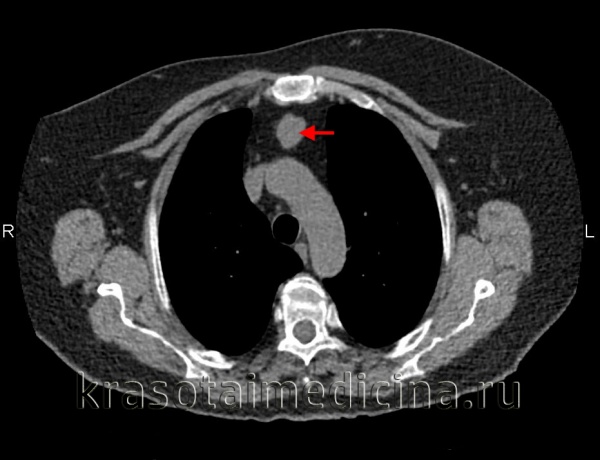

Обязательный перечень рентгенологических исследований включает рентгенографию грудной клетки, рентгенографию пищевода с контрастированием, компьютерную томографию. В большинстве случаев проведенное обследование позволяет установить локализацию рака средостения и распространенность процесса, заинтересованность органов грудной полости (легких, диафрагмы, аорты, грудной стенки). Уточнить состояние мягких тканей в зоне новообразования, выявить метастазы опухоли в лимфоузлы и легкие помогает МРТ.

- Томографическая диагностика. Для более детальной оценки структуры, толщины стенок кисты, характера содержимого и взаимоотношения с соседними анатомическими образованиями, производится КТ и МРТ средостения.